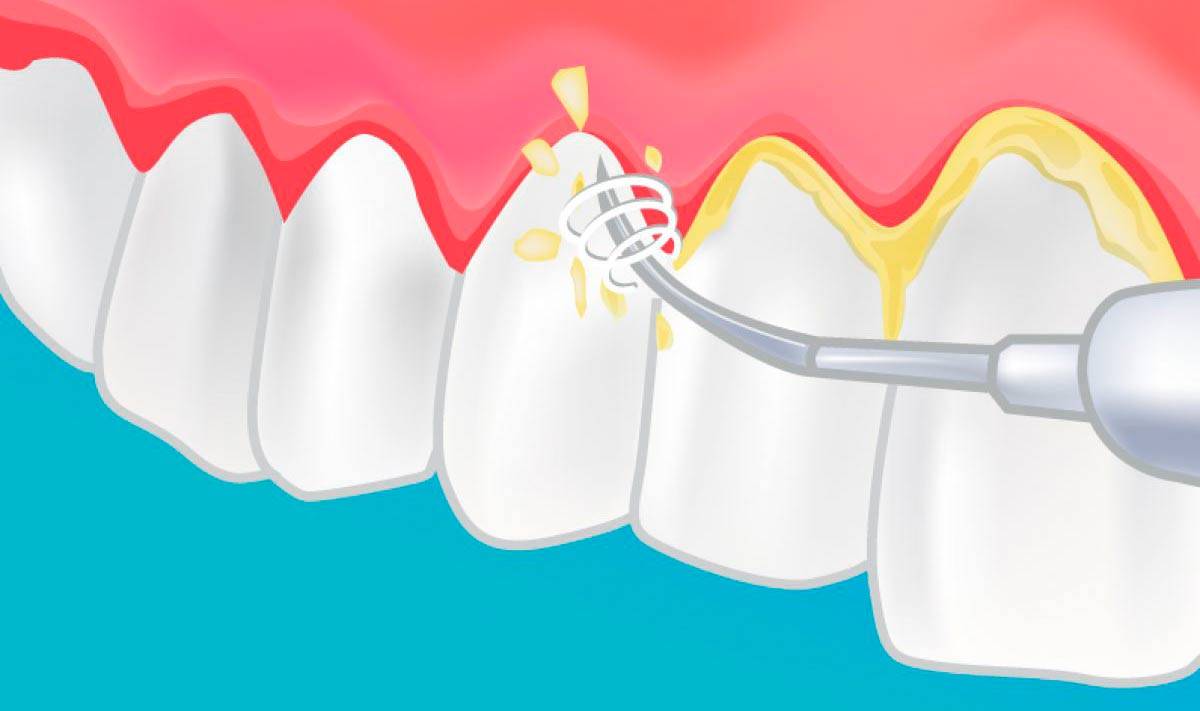

Как ставятся брекеты: санация ротовой полости

После установки брекетов заметно усложняется процедура чистки зубов и повышается риск развития кариеса. Чтобы снизить его к минимуму, нужно устранить все кариозные полости. Основная задача стоматолога — выявить скрытые очаги патологии, которые расположены в межзубных пространствах.

Также необходимо устранить воспалительные процессы, если они были обнаружены во время диагностики. Иными словами, нужно вылечить те патологии, которые могут осложниться после установки брекетов. Кроме того, на подготовительном этапе проводится ультразвуковая чистка, в процессе которой удаляются налет и зубные камни.